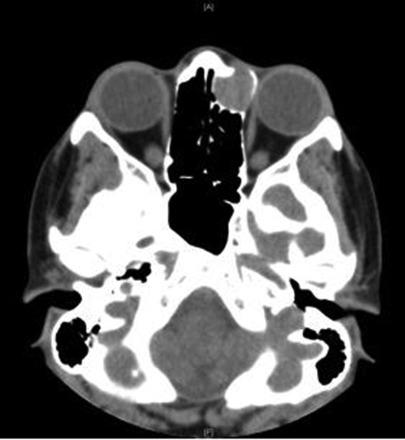

This was an unusual case of lacrimal sac compression by an anterior ethmoidal mucocele presenting as a late complication of a dacryocystorhinostomy (DCR) that was jointly managed by ophthalmic and ENT surgeons via an endoscopic approach. A 22-year-old lady presented with a 12-month history of a painless lump in her left medial canthus area and a 6-month history of left intermittent epiphora. She had a DCR when she was 15 years old with initial symptom control until recent recurrence. There were no nasal or other eye symptoms. The rest of the eye and nasendoscopic examinations were unremarkable. An MRI scan suggested a dacryocystocele; however, a further CT scan revealed a 1.6 cm cystic lesion consistent with an anterior ethmoidal mucocele compressing the lacrimal sac. An endoscopic left anterior ethmoidectomy with marsupialisation of the mucocele was performed in combination with an endoscopic DCR. She made good post-operative recovery.

这是一例不寻常的病例,即筛窦黏液囊肿压迫泪囊,表现为泪囊鼻腔吻合术(DCR)的晚期并发症,由眼科和耳鼻喉科医生通过内镜方法联合处理。一名22岁女性,左侧内眦区出现无痛性肿块12个月,左侧间歇性溢泪6个月。她15岁时接受了DCR,最初症状得到控制,直到最近复发。无鼻部或其他眼部症状。眼部其他检查及鼻内镜检查均无异常。MRI扫描提示泪囊膨出;然而,进一步的CT扫描显示一个1.6 cm的囊性病变,符合筛窦黏液囊肿压迫泪囊。在内镜下行左侧前筛窦切除术并对黏液囊肿进行袋形缝合,同时行内镜下DCR。术后恢复良好。